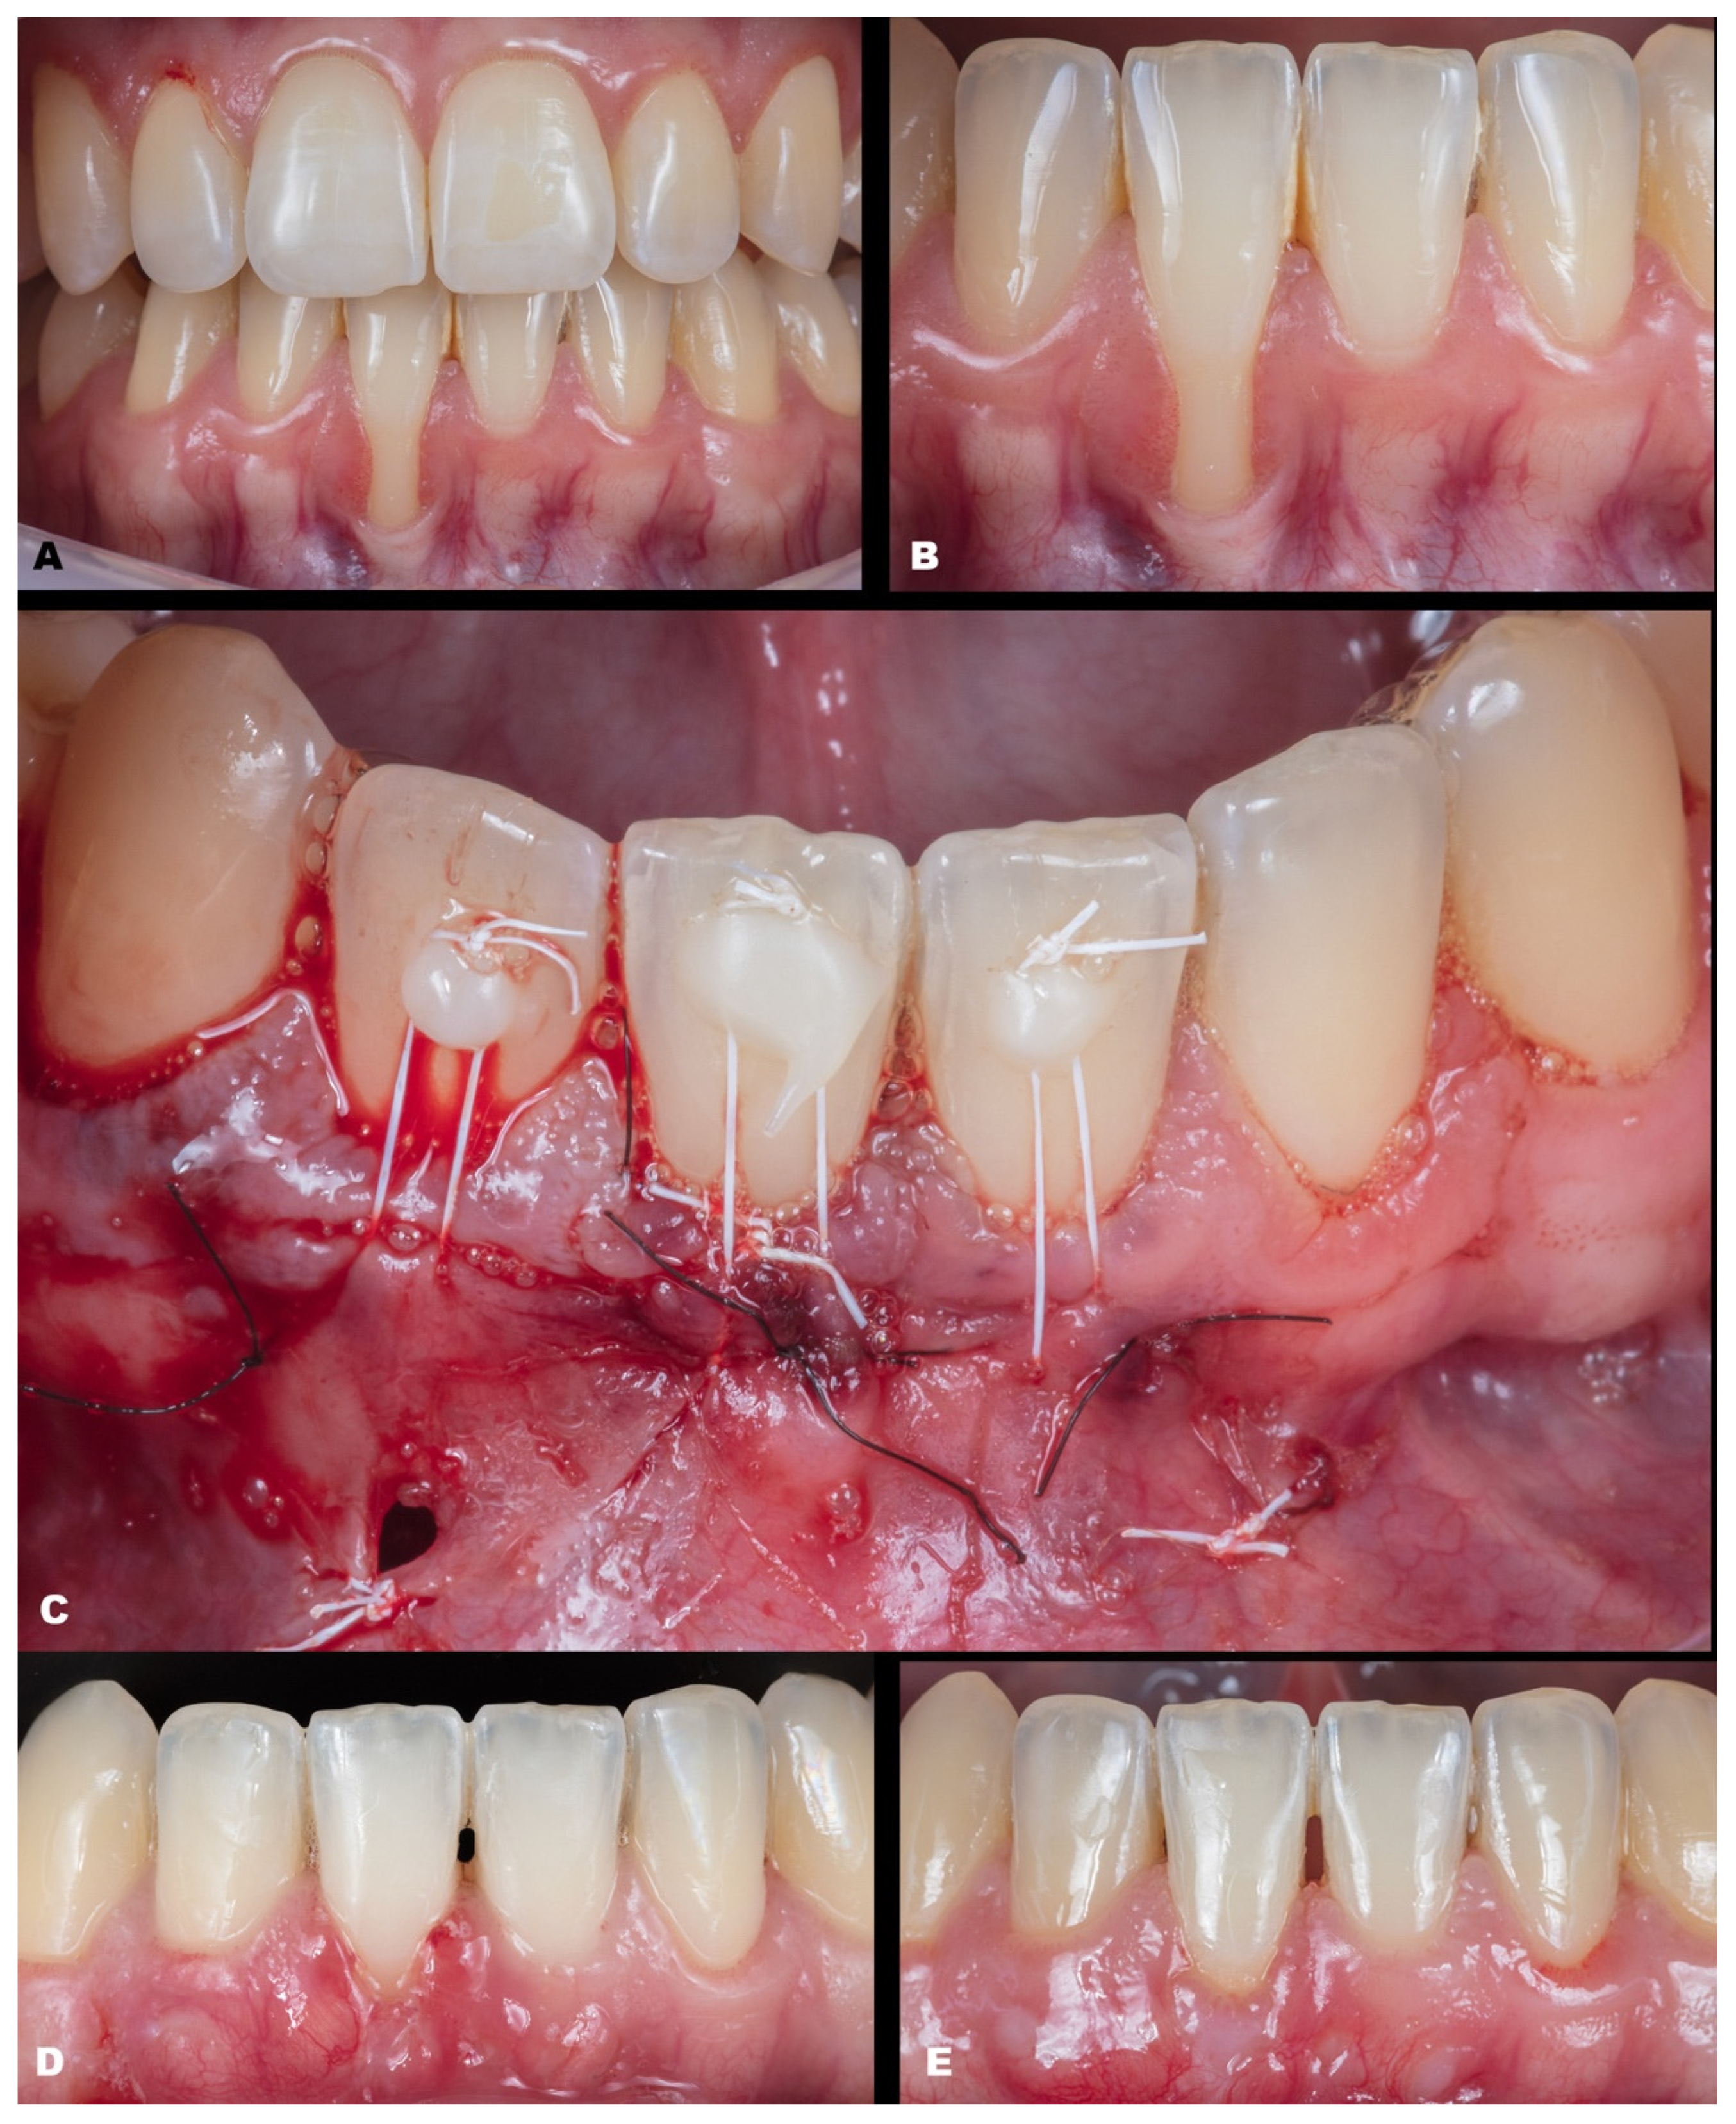

| Classification | Gender | Tooth/Teeth with REC | Initial REC Height (mm) | Initial REC Width (mm) | Initial PD (mm) | Initial KTW (mm) | Final REC Height (mm) | Final PD (mm) | Final KTW (mm) | % RC | p-Value | |

|---|---|---|---|---|---|---|---|---|---|---|---|---|

| Baseline | 6-Month Follow-up | |||||||||||

| Case 1 | RT2 | M | 41 | 6.2 | 2.5 | 1.0 | 0.3 | 1.1 | 2.0 | 4.3 | 82.25 | REC: p < 0.0001 PD: p = 0.2771 KTW: p = 0.1013 |

| Case 2 | RT1 | F | 31 | 3.3 | 1.7 | 0.5 | 0.3 | none | 1.0 | 3.7 | 100 | |

| Case 3 | RT1 | F | 41 | 1.2 | 2.1 | 1.0 | 3.3 | none | 0.5 | 7.3 | 100 | |

| Case 4 | RT1 | F | 41 31 | 1.4 1.2 | 2.1 1.8 | 1.0 0.5 | 3.1 2.9 | none | 1.0 0.5 | 3.7 4.0 | 100 100 | |

| Case 5 | RT1 | M | 43 | 1.5 | 2.3 | 1.0 | 1.3 | none | 1.5 | 4.4 | 100 | |

| Case 6 | RT1 | F | 43 44 45 | 1.2 2.1 1.4 | 2.6 3.1 2.8 | 2.0 1.5 1.0 | 3.0 3.8 3.8 | none | 1.5 1.0 1.0 | 2.1 2.8 5.3 | 100 100 100 | |

| Case 7 | RT1 | F | 12 11 21 22 | 1.1 1.5 2.4 1.5 | 1.5 3.0 4.0 2.0 | 1.0 2.0 1.5 2.0 | 5.4 5.0 6.3 6.9 | none | 1.0 2.5 2.5 1.5 | 4.3 5.7 6.0 6.3 | 100 100 100 100 | |

| Case 8 | RT2 | F | 42 41 31 32 | 2.2 3.4 3.2 1.2 | 2.3 2.5 3.0 2.7 | 0.5 0.5 0.5 1.0 | 2.4 1.9 1.5 3.5 | 0 0.6 0.6 0.5 | 1.5 1.0 1.0 1.0 | 3.6 2.9 2.1 3.3 | 100 82.35 81.25 58.34 | |

| Case 9 | RT1 | F | 12 13 | 1.3 2.1 | 2.2 2.3 | 1.5 2.0 | 4.4 5.3 | none | 2.5 1.5 | 4.6 5.2 | 100 100 | |